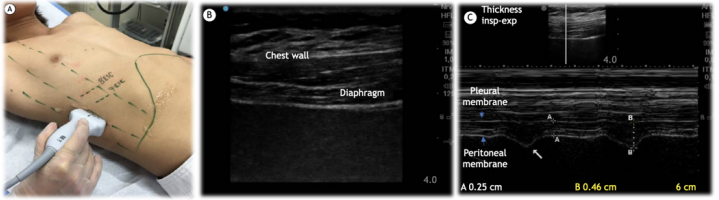

临床中进行膈肌管理要秉持的基本思路和方法主要包括四部分:①风险识别和防治:例如脓毒性休克,血管活性药物或激素的使用,营养不良,高强度有创机械通气等。患者越快度过危重期,膈肌功能保留就越好,后期撤机就越简单。②膈肌的训练:要采用各种手段,使患者的膈肌动起来,包括尽早恢复自主呼吸和膈肌活动,呼吸支持力度降阶梯,PSV模式,膈神经起搏,膈肌阻抗训练等。③膈肌功能评估:包括评估最大吸气压(MIP),通过超声评估膈肌厚度、变异度及膈肌活动度。④膈肌做功状态评估:识别患者的异常呼吸状态及呼吸疲劳,评估辅助呼吸肌的参与、呼吸驱动及人机同步性。2022年四川大学华西医院周永方等在Crit Care发表了一项随机对照研究,证明了浅镇静可以缩短患者机械通气时间,提高拔管成功率。笔者团队的经验是,浅镇静和早期膈肌锻炼是防治膈肌功能障碍最有效的手段。我们的目标是通过浅镇静和自主通气模式来使患者维持接近自然呼吸的驱动,丙泊酚和右美托咪定可能最契合。同时,在使用PSV模式时,设置PS使患者的呼吸驱动在正常范围。如果短时间内患者的自主呼吸不能完全恢复,或由于某些情况不能短时间内唤醒,或因为神经功能障碍等问题短时间内不能拔管,患者长期带机很可能导致膈肌萎缩,此时就需要通过膈神经起搏来预防膈肌衰弱。膈神经起搏目前尚处于研究阶段,但有些医院已将其作为常规的治疗手段,该方法更多是预防膈肌萎缩。其机制是通过体外膈肌起搏器刺激膈神经使膈肌运动,进而达到预防膈肌萎缩的目的。已有动物实验证实有创机械通气期间的膈神经起搏可以降低膈肌纤维的变薄趋势。也有研究发现机械通气期间的膈神经起搏可以降低膈肌变薄趋势。最早的膈肌起搏是体内植入电极,主要用于有外周神经系统功能障碍患者,可以通过中心静脉给予刺激,也可以在患者锁骨中线第二肋间处植入起搏器。对于重症患者,通常采取体外膈肌起搏(EDP),在体表靠近膈神经处贴1~2组电极片,连接刺激器。每天2次,每次30 min,每周5天,频率为8~20次/min,能够预防膈肌萎缩。该方法通常需要进行质控。通过监测患者的呼吸机波形、膈肌超声以及患者主诉/面容等了解治疗情况。3. 膈肌训练—drive the diaphragm膈肌训练一般是通过膈肌阻抗训练来完成。也有学者认为重症患者早期下床活动可以达到锻炼膈肌的效果,但目前没有得到研究证实。我们通常所说的膈肌训练指的就是膈肌的阻抗训练,并且是目前唯一被高质量研究证实的可以改善患者膈肌功能的治疗措施。2023年Eur Respir Rev杂志发表的研究表明,膈肌阻抗训练能够增加患者的MIP、提高生活质量。目前机械式膈肌阻抗训练器有两种类型,一种是流阻负荷训练器,另一种是阈值负荷训练器。流阻负荷训练器是通过调节旋钮孔径的大小来调节吸气阻力,孔径越小阻力就越大。缺点是比较依赖于患者的吸气流速。所以在整个训练过程中其阻力是不稳定的,效果可能也不如预期。而阈值负荷训练器的的阻力在整个训练过程中比较稳定,能够比较好地保证训练效果。目前的研究大都推荐首选阈值负荷训练器。无论是健康人还是慢阻肺人群,阈值负荷训练器的压力都更稳定,训练效果更佳。机械式阻抗训练器可以直接连接人工气道。在机械式阻抗训练器缺乏的情况下,也可以将呼吸机的触发方式改为压力触发,增加压力触发灵敏度的数值,也就是增加触发难度,同样可以达到训练的目的。此外,如果患者膈肌功能特别差,也可以接螺纹管,训练几天后再过渡到上述两种方法。膈肌训练的原则是高强度、低频率。如果患者能够配合,可以直接采用手持式测力器或简易肺功能仪来测量。如果患者配合度不好,或患者镇静尚未清醒,可以通过呼吸机的NIF或MIP功能,长按20~25 s来读数,可以测量患者的MIP,测出后从50% MIP设置,连续6次呼吸,每天5组,每周不少于5天,组间休息1~2 min。按照MIP的50%设置阻力强度。膈肌训练适应证:机械通气预计或已经达到1周以上。训练方法:训练器、增加呼吸机触发难度;MIP过低的患者,可以使用螺纹管。需要每天滴定阻力值,至患者刚好完成连续6次呼吸,而不引起明显膈肌疲劳。正常来讲,如果训练效果好,患者MIP平均每天会增加1 cmH2O。澳大利亚重症指南推荐患者至少坚持训练2周。最好能坚持1个月。训练期间注意加强心理辅导和营养支持。体外膈肌电刺激和膈肌训练是目前在ICU中针对膈肌的治疗和训练。除了训练,还要注意做好膈肌功能的评估,判断治疗后患者膈肌功能有无好转。常用的评估方法有膈肌超声。(1)膈肌超声:膈肌超声有两个测量位置,一个是在锁骨中线与肋弓下缘交界处,测量膈肌的移动度。如图1B和D所示高亮白线就是膈肌的位置,在患者正常呼吸时,采用M模式测量浅呼吸和深呼吸下膈肌的移动度。另外一个测量位置是在腋中线或锁骨中线8~10肋间,通过M模式测量膈肌在吸气末和呼气末的厚度(如图2所示),从而判断膈肌做功情况以及膈肌增厚率,这些参数能够反映膈肌功能。此外,膈肌超声还可以帮助判断膈肌是否萎缩、衰弱,并预测撤机风险。表1所示为安静呼吸、深呼吸和鼻息试验时膈肌的正常移动度。如果测得的患者膈肌移动度低于表中数值,说明患者膈肌已经萎缩。Intensive Care Medicine杂志发表的一篇综述中给出了诊断建议:如果患者最大膈肌增厚分数<20%,可以认为该患者存在膈肌萎缩或膈肌无力;或嘱患者做深呼吸,观察患者最大膈肌移动度是否超过1 cm,也可以帮助判断患者有无膈肌萎缩。